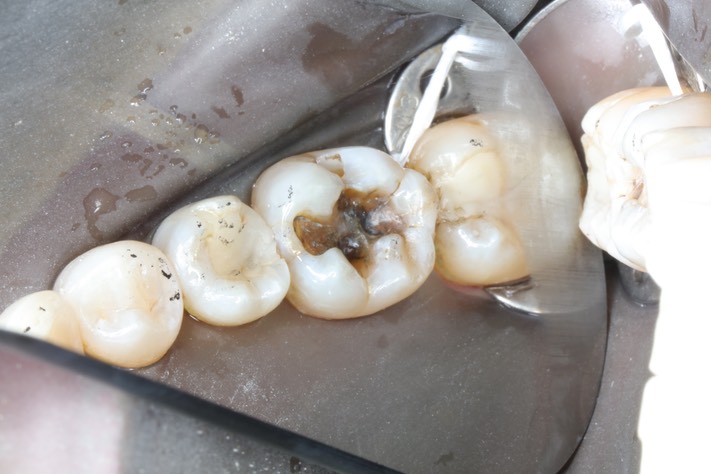

Chris Woo #19 amalgam removal